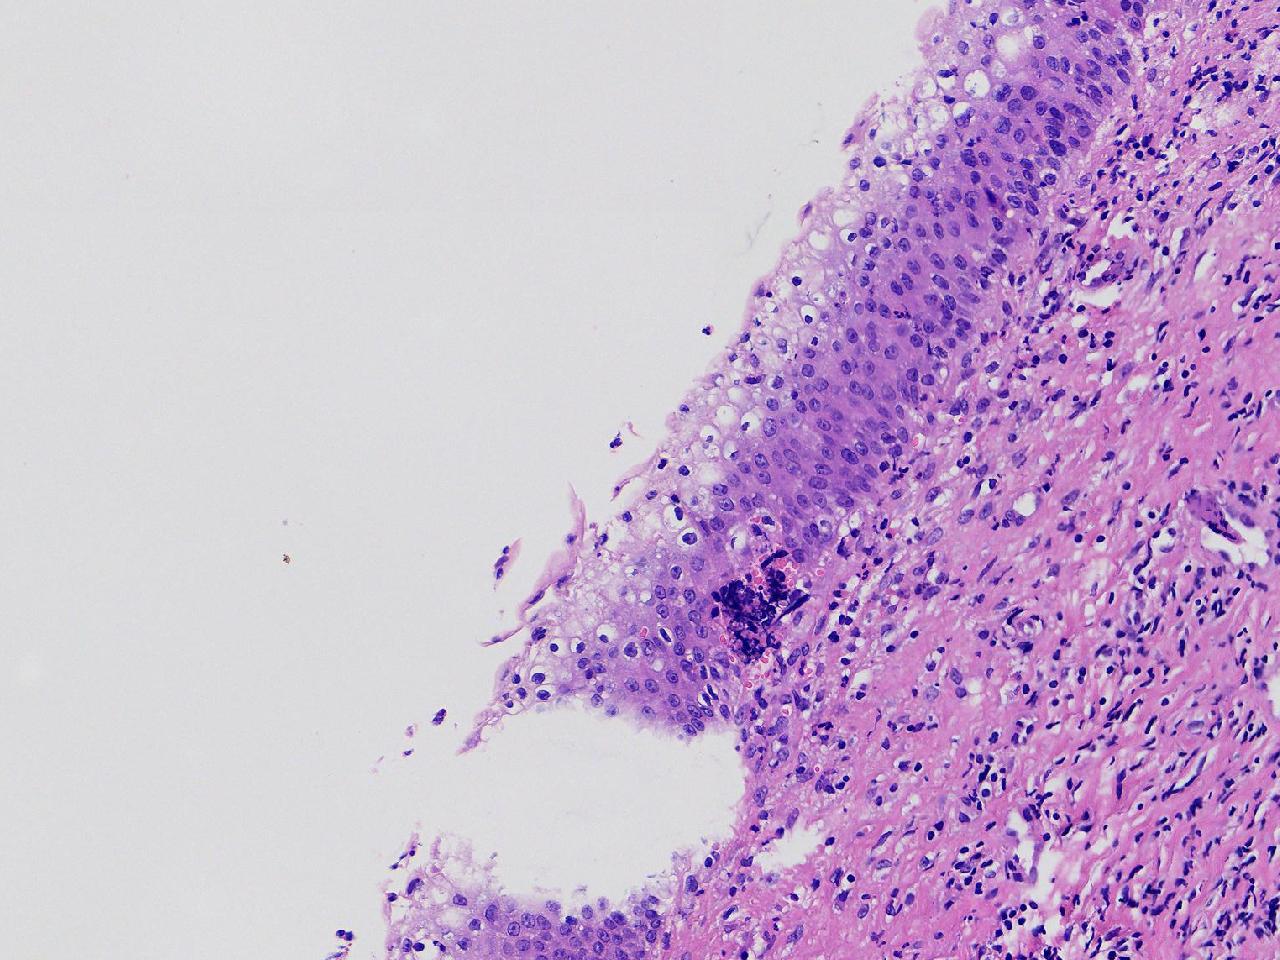

女,59岁,宫颈活检,TCT报告ASC—US, HPV不详。

宫颈多点活检。

灰白色不整形软组织多块。

CIN1,建议HPV检测

高级别